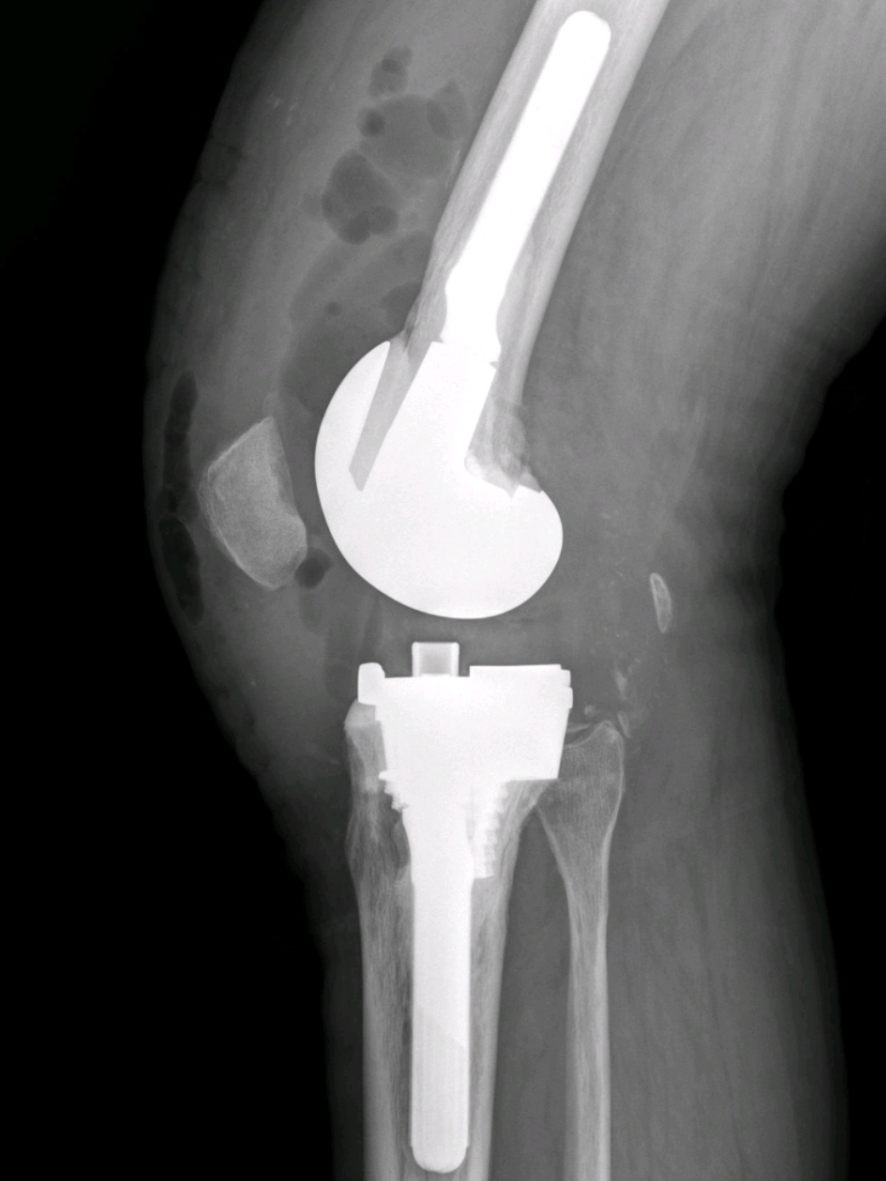

与初次关节置换相比,翻修术对手术医生、患者都具有挑战性。潘永德迅速组织了会诊,经过多次深入讨论,最终为陈大叔量身定制了一套详细的手术方案。在清华长庚医院陈连旭教授的指导下,历经6个小时,关节外科团队成功为患者行“右侧全膝关节假体翻修术”。

全膝关节假体翻修术后

术后,陈大叔在医护人员的精心照料下,逐渐恢复了健康。医生们定期为他进行康复指导,帮助他进行膝关节的功能锻炼。同时,他们还对陈大叔进行了全面的检查,确认他的膝关节没有出现感染、假体移位等并发症,这让他和家人都感到无比的欣喜和感激。